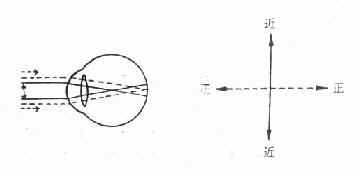

1.单纯性散光:一条主经线为正视,另一条主经线为远视(单纯远视散光)或近视(单纯近视散光)。

图16-9 单纯近视散光